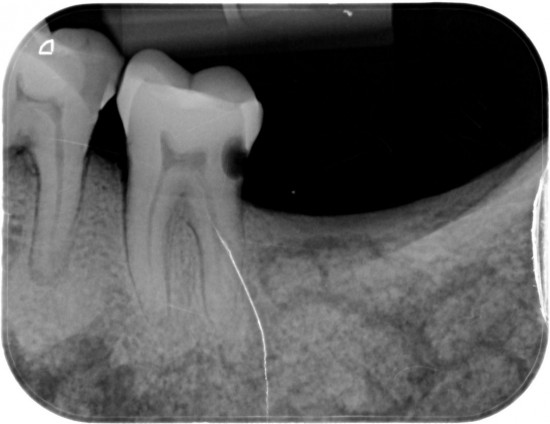

Tanden op kaakdeel (Links)     M3 derde kies (verstandskies ontbreekt )  M2 tweede grote kies half gebroken . M1 eerste grote kies.half gebroken

.P2 tweede kleine kies .P1 eerste kleine kies ontbreekt  , een hoektand , twee snijtanden .

Van de M2 en de M1  (Links) werden  extra rontgenfoto,s gemaakt om  duidelijk te maken dat het niet een maar  twee aparte kiezen betrof .

Duidelijk zichtbaar de wortels van beiden tanden ..

Verder was goed zichtbaaar de vergaande  botontsteking bij de gebroken kiezen .